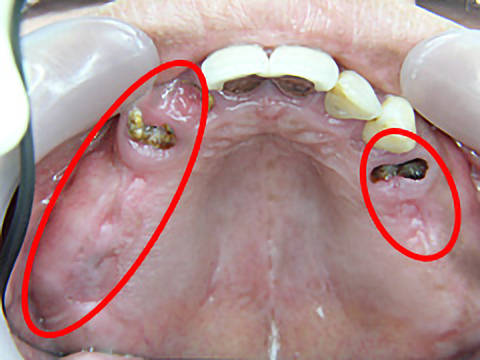

症例3

年齢 | 42歳 |

---|---|

性別 | 女性 |

費用 | 1本あたり330,000円+保険で必要な金額(抜歯など) |

治療期間/治療回数 | 1年半/20回 |

治療におけるリスク |

骨の状態により治療ができない場合があります。 一度埋め込んだインプラントが脱離する可能性があります。 上部構造は消耗品です。一生持つものではなく、破折する可能性があります。 |

歯科治療が怖くて長きにわたりお口を放置されていましたが、一大決心の後、当院にて治療を受けられました。

右上4本、左上も3本、抜歯即時埋入を含めてインプラント治療を受け、噛み合わせを取り戻すことができました。また、下顎の前歯も大きくすり減っていたため、オールセラミックスで治療しました。